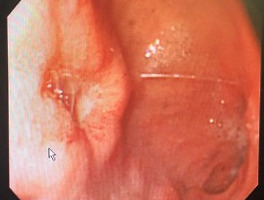

가. 내시경 등으로 위 및 십이지장의 소화성궤양(반흔기 포함), 저등급 MALT 림프종(low grade gastric mucosa associated lymphoid tissue lymphoma)이 확인된 환자

1) 내시경 등으로 위 및 십이지장의 소화성궤양(반흔기 포함)이 확인된 환자로서

1) 헬리코박터파일로리에 의한(H. pylori 균주 확인) 소화성궤양에 헬리코박터파일로리 박멸요법이 필요한 경우

가. 소화성궤양